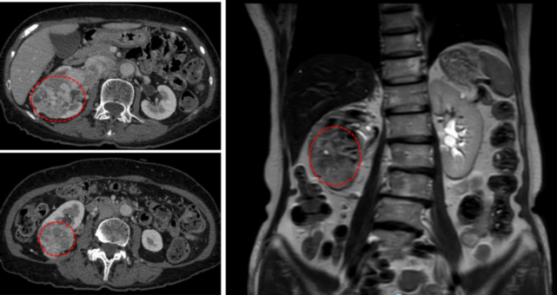

84岁的香港籍关阿婆因“右腹部疼痛加重并发现右肾占性病变位1月余”慕名来我院泌尿外科刘久敏主任医师门诊就诊。刘主任接诊后经过详细的检查,诊断患者为:右肾癌(T3N0M0)伴腔静脉癌栓(Mayo Clinic III级)。患者的肿瘤影像学结果提示:肿瘤约70*59*71mm,且瘤体已经侵犯右侧肾周脂肪、肾盂、右肾静脉并生长进入下腔静脉。更为复杂的是,通过CT和MR重建动静脉血管影像发现瘤体血供异常丰富,瘤体内分布粗大肿瘤血管;癌栓范围较大并且局部可疑侵犯下腔静脉血管壁。

(患者影像学检查结果)